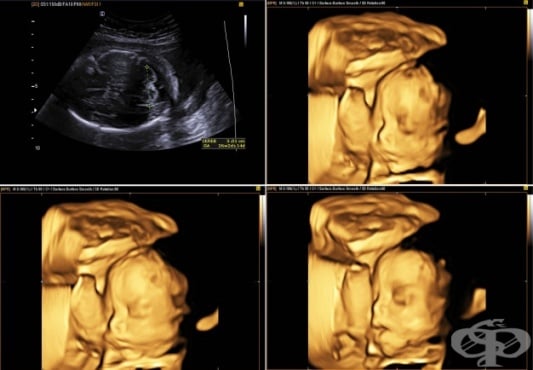

Устата, носа и устните на бебето могат да бъдат разпознати при ултразвуковото изследване. |

Ръцете и краката на бебето се движат. Това ще се види на ултразвука. |

Вашето бебе ясно вече изглежда като бебе. |